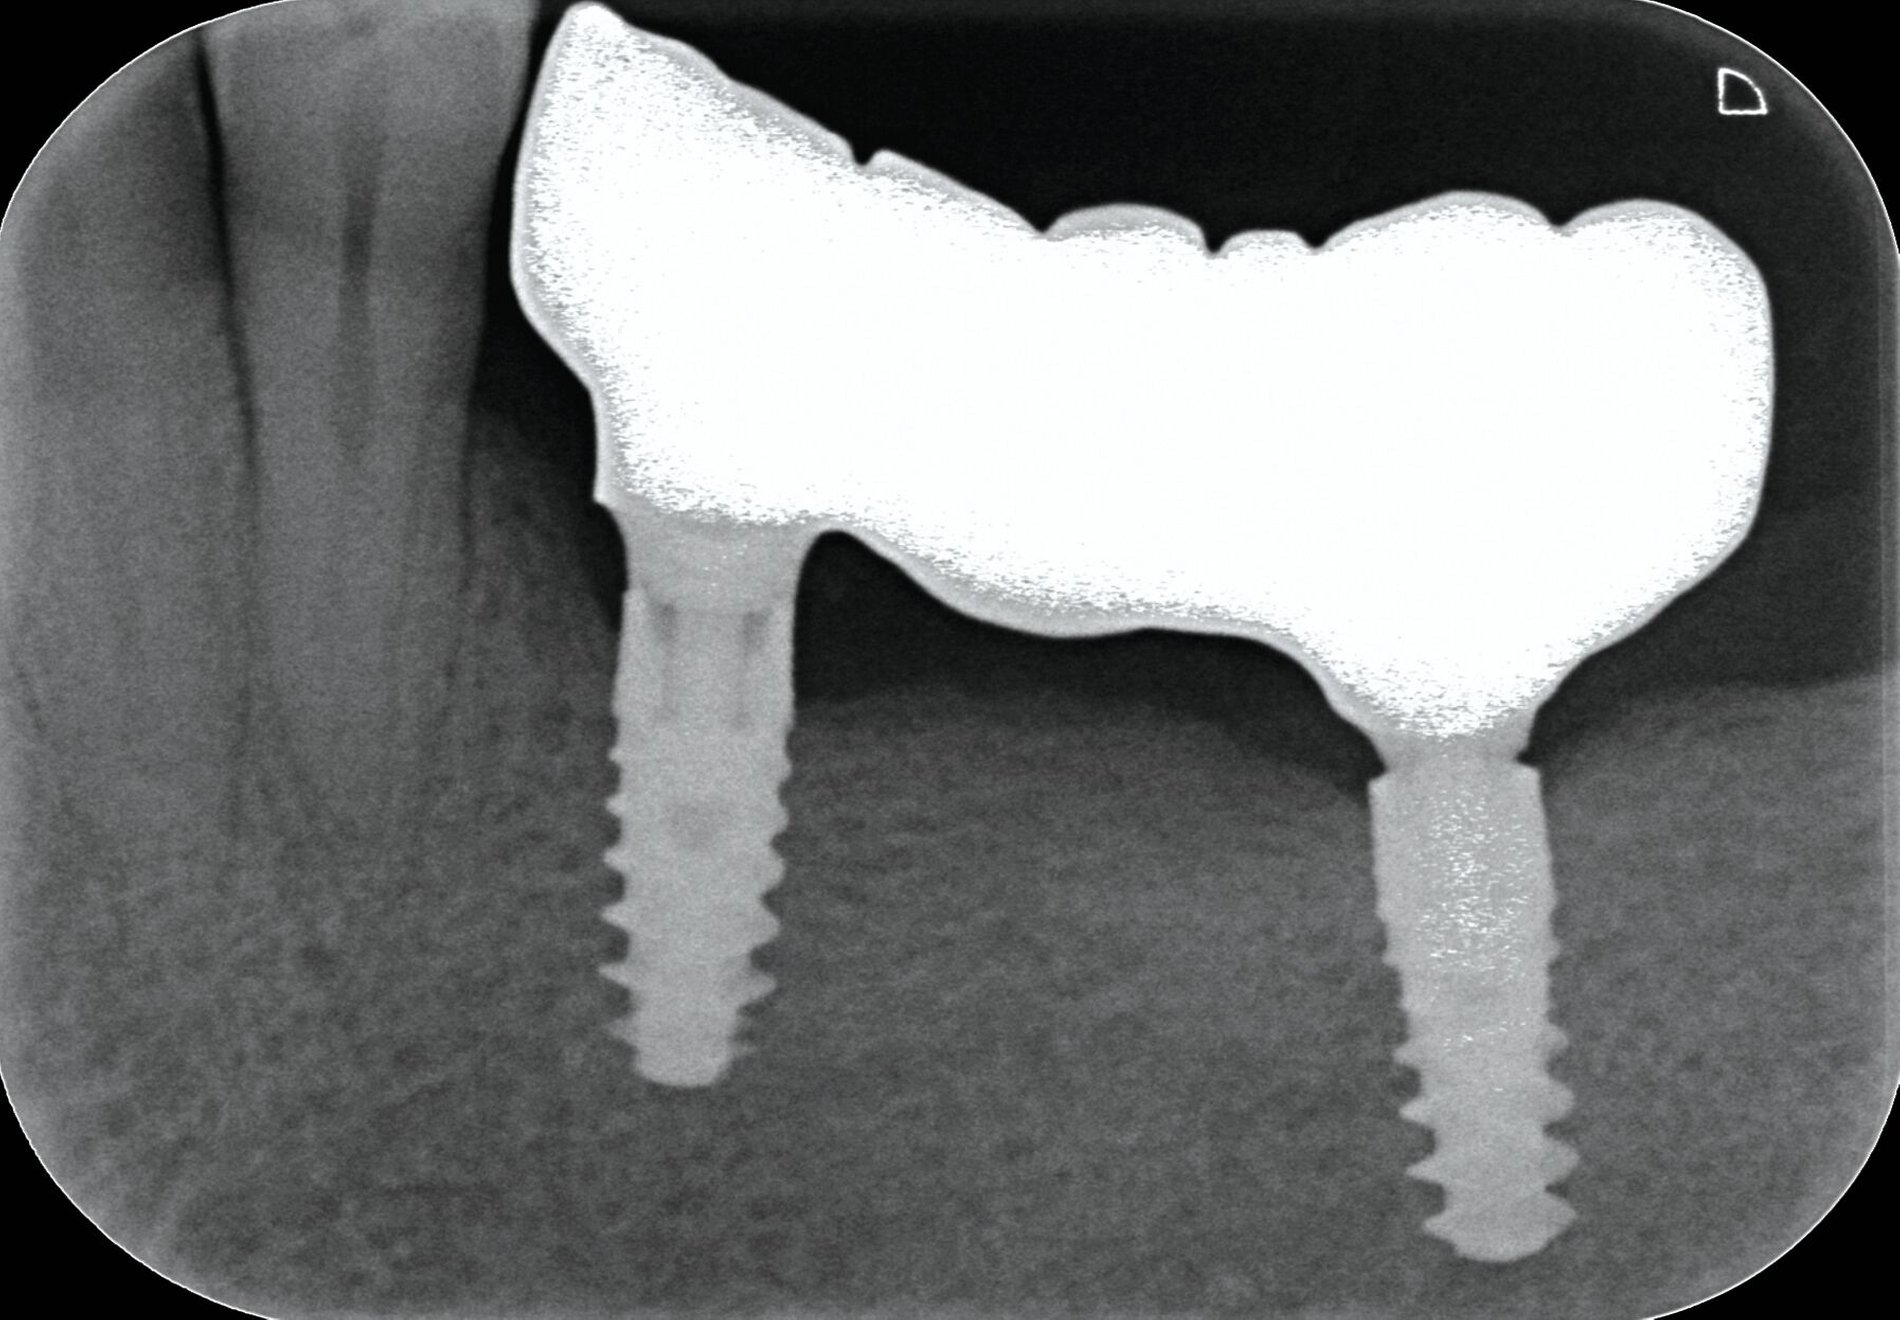

Das Abutment war oberhalb der Implantat-Schulter gebrochen. Obwohl die Befestigungsschraube mit dem Standardwerkzeug einfach zu lösen war, ließ sich das Abutment-Fragment nicht entfernen. Also wurde das Restfragment mit einem Spezialwerkzeug (Konus-Adapter mit Linksgewinde für die passende Ratsche) entfernt. Wichtig ist dabei, darauf zu achten, dass das Innengewinde nicht verformt wird. Um ein zu festes Eindrehen zu vermeiden, kann dies mittels eines Zahnfilms überprüft werden (Abbildung 1). Nach der Lageüberprüfung wird der Konus-Adapter mit circa 30 – 35 Ncm festgezogen und das Fragment durch Rütteln entfernt. Sollte dies nicht zum Erfolg führen, kann man mittels Ultraschall auf den Adapter einwirken (Abbildung 2).

Das herstellerseitig empfohlene Vorgehen sieht vor, das Abutmentfragment zentral mit einem runden Bohrer oder Diamanten (Ø 1,2–1,4 mm) anzukörnen. Anschließend erfolgt die Bohrung mit einem speziellen Kernlochbohrer (Ø 1,8 mm, Tiefe circa 3 mm) bei 1800 U/min und unter Kühlung. Ein passender Extraktionsstift wird eingeschraubt und das Schraubenfragment mithilfe eines Ausdrehers entfernt. Für verbliebene Gewindehülsen stehen spezielle Ausdrehinstrumente zur Verfügung; in schwierigeren Fällen kann zusätzlich ein Spiralbohrer (1,4 mm) zum Einsatz kommen. Der finale Schritt besteht in der Nachbearbeitung des Innengewindes mit einem Gewindeschneider (M1,8). Zur Minimierung des Friktionswiderstands kann die Verwendung eines Gleitmittels (zum Beispiel Vaseline) hilfreich sein. Ein verkantungsfreies Arbeiten ist essenziell, um Instrumentenbruch und Implantatverlust zu vermeiden. Die radiologische Darstellung des Bruchs sowie die Situation nach Entfernung der Komponenten sind in den Abbildungen 3 und 4 dokumentiert.